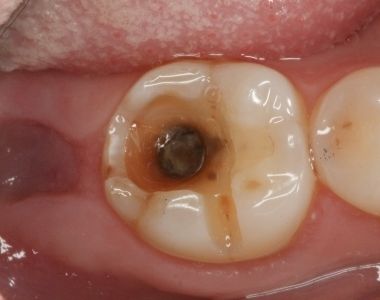

我们可以结合这张图

▼

这就是所谓的——小洞不补,大洞吃苦。

第二阶段:牙齿出现小黑洞,说明引起中度蛀牙,细菌腐蚀来到牙本质,伴随着牙齿敏感,黑色腐败物质其实就是细菌的产物,这时候还可以再补牙;